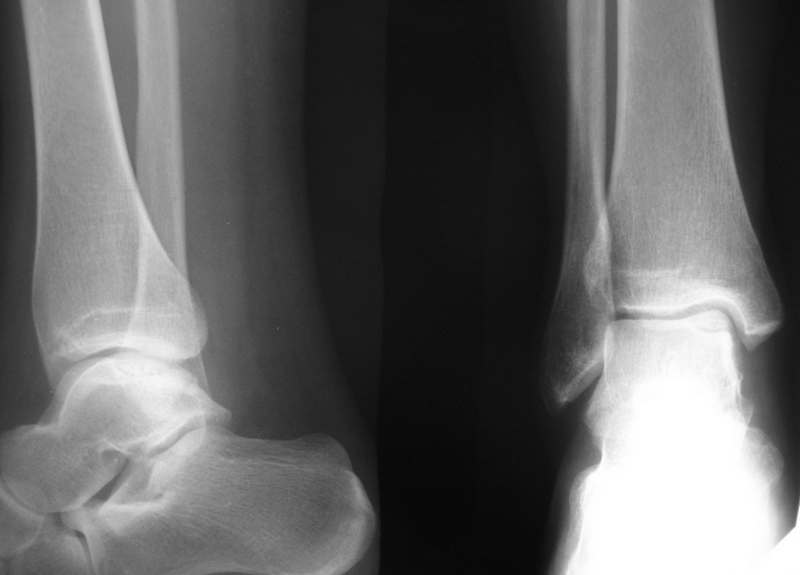

Больная М., 30 лет, около полугода беспокоят боли в голеностопном суставе. На

рентгенограммах и КТ признаки остеохондропатии блока таранной кости.(РКТ на бумаге

поэтому не выкладываю) Выносится на обсуждение тактика: 1. Просто ждать, назначив

разгрузку сустава, физиолечение, ЛФК. 2. Артротомия сустава, фиксация винтом типа

Герберта. 3. Артроскопия или артротомии с удалением фрагмента.